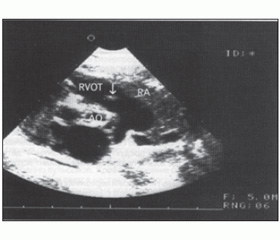

При проведении ультразвукового исследования (рис. 1) определяются следующие признаки: деформация и сращение створок аортального клапана; ограничение их подвижности; уменьшение отверстия аортального клапана в систолу при поперечном сечении корня; куполообразный изгиб створок; появление систолического турбулентного потока в восходящем отделе аорты; регистрация трансаортального градиента давления и др.

— ЭхоКГ: определяет деформированные створки клапанного аппарата, выбухающие в просвет аорты. Допплерэхокардиография регистрирует высокоскоростной турбулентный поток крови на уровне клапана;